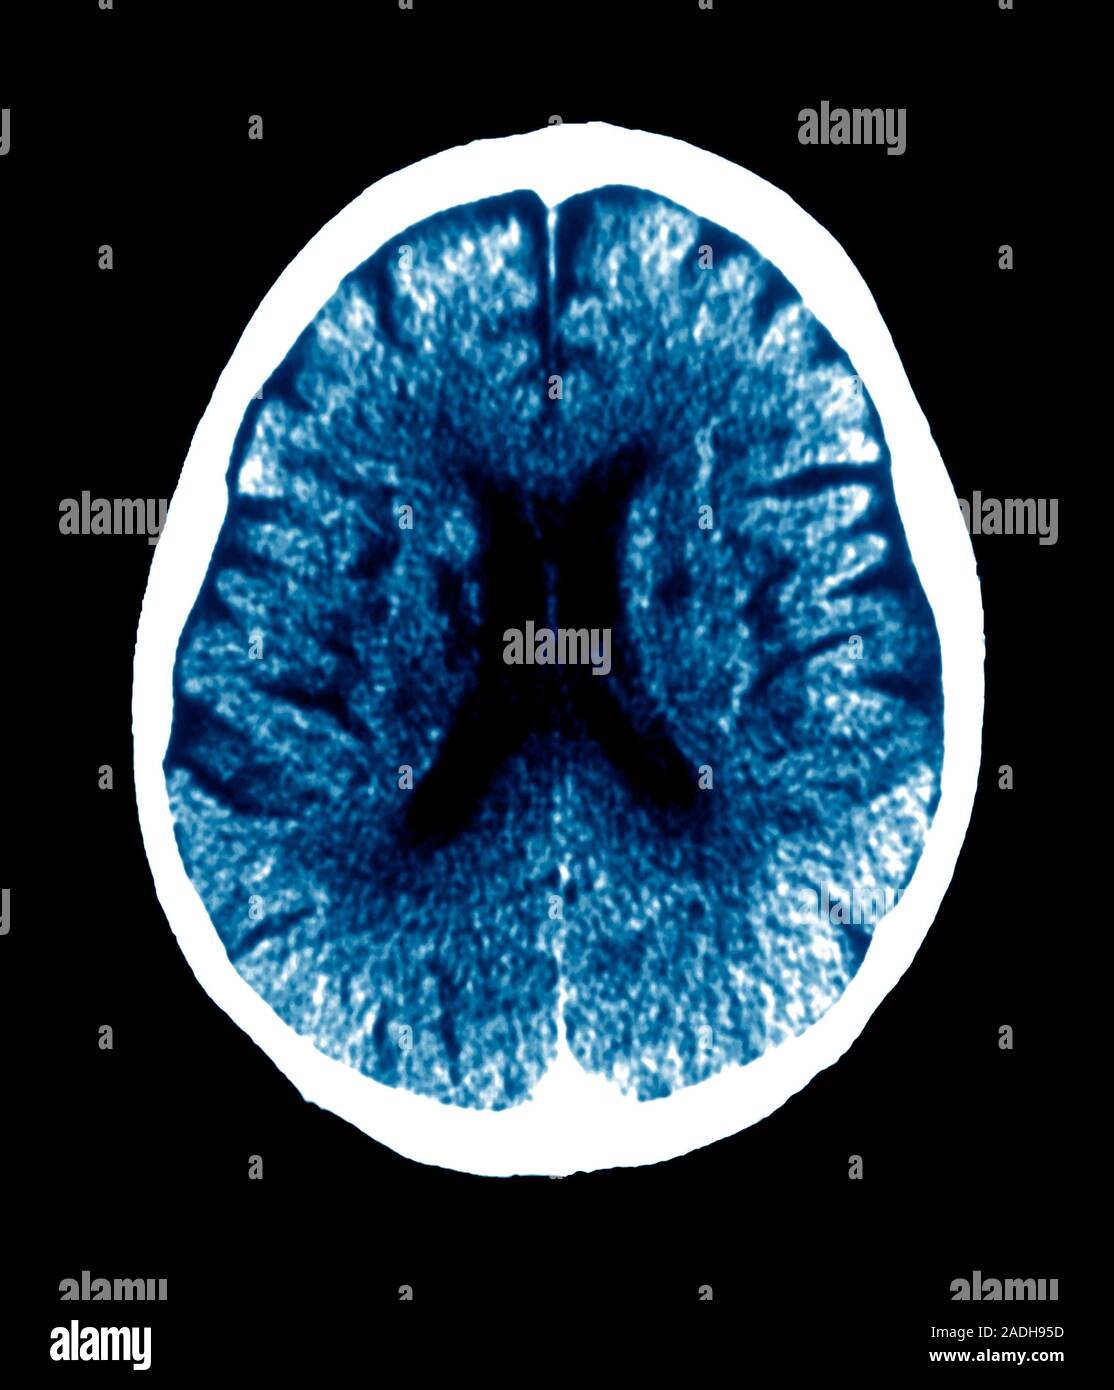

Binswanger's disease. Coloured axial computed tomography (CT) scan of Binswanger Disease Binswanger disease is a progressive neurological disorder caused by arteriosclerosis and thromboembolism affecting the blood. Binswanger's disease is a type of dementia caused by atherosclerosis of subcortical arteries in the brain. Vascular dementia is a type of dementia caused by reduced blood flow to the brain. It can lead to dementia, parkinsonism, and other neurological abnormalities. Subcortical arteriosclerotic encephalopathy, also. Binswanger Disease.